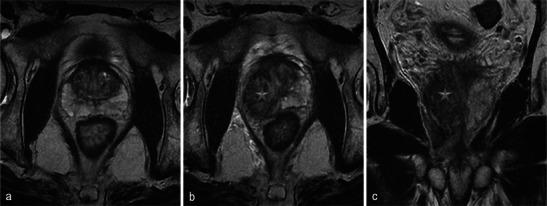

In this technique, a photosensitising agent is introduced intravenously, then activated by local laser illumination to induce tumour necrosis. Treatment efficacy is assessed by magnetic resonance imaging (MRI).

We illustrate specific post-treatment MRI aspects at early and late follow-up with pathological correlations.

• Dynamic phototherapy is a new and promising focal therapy for prostate cancer. • One-week MRI shows increased volume of the treated lobe and large, homogeneous necrosis area. • Six-month MRI shows significant changes of the prostate shape and signal. • Six-month MRI becomes "base line" appearance for further follow-up or monitoring.

在该技术中,将一种光敏剂静脉注射,然后通过局部激光照射激活以诱导肿瘤坏死。通过磁共振成像(MRI)评估治疗效果。

我们阐述了早期和晚期随访时特定的治疗后MRI表现及其与病理的相关性。

• 动态光动力疗法是一种用于前列腺癌的新型且有前景的局部治疗方法。• 一周后的MRI显示治疗叶体积增大以及大片均匀的坏死区域。• 六个月后的MRI显示前列腺形态和信号有显著变化。• 六个月后的MRI成为进一步随访或监测的“基线”表现。